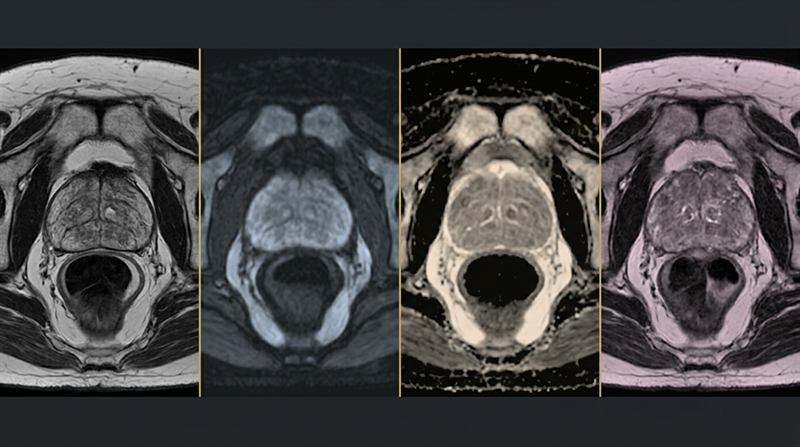

Multiparametric MRI

Multiparametric magnetic resonance imaging (mpMRI) is a powerful new tool which is changing the landscape of prostate cancer8.

Read more...